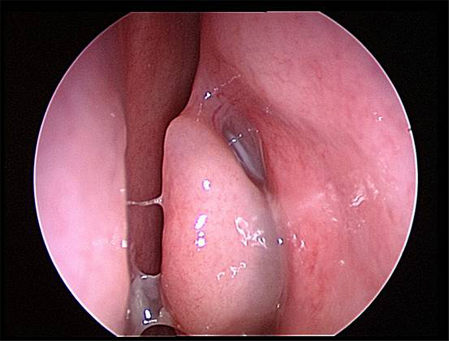

[Figure caption and citation for the preceding image starts]: Meato médio esquerdo com edema grave e secreções purulentasDo acervo de Melissa Pynnonen, MD [Citation ends].

[Figure caption and citation for the preceding image starts]: Meato médio esquerdo com mucosa saudável e secreções não purulentasDo acervo de Melissa Pynnonen, MD [Citation ends].